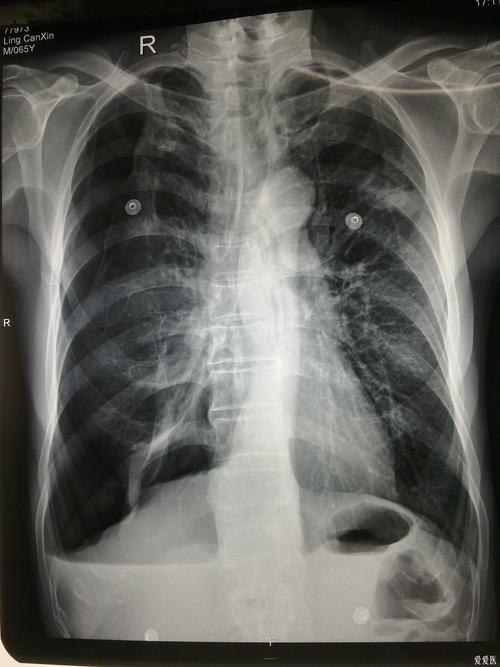

典型的结核病人液气胸胸片

气胸胸片典型图片

气胸胸片

气胸的x线表现

液气胸